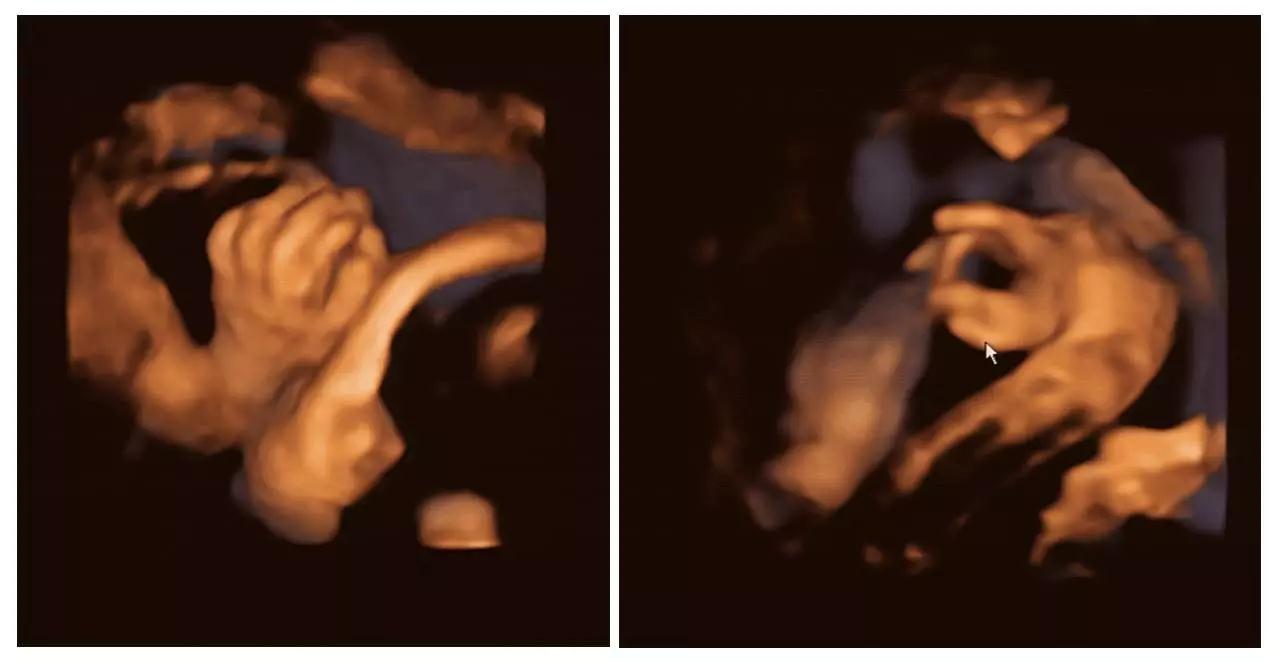

(右手多指畸形)